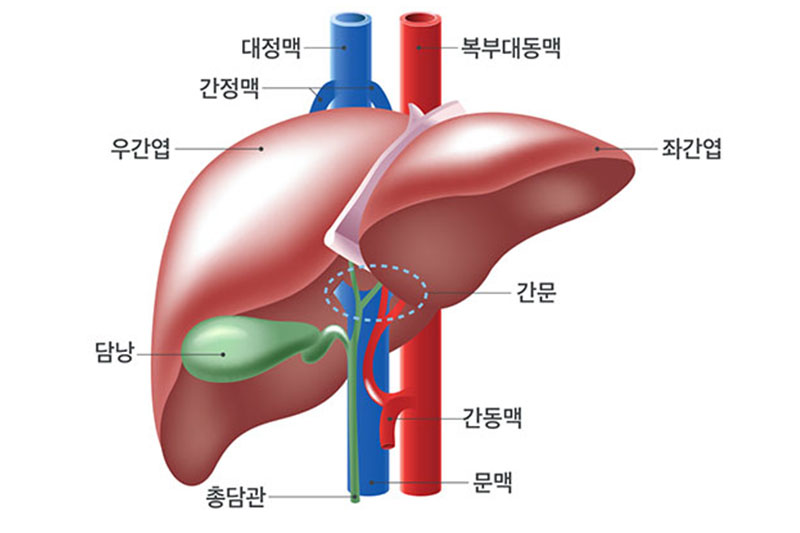

발생부위

간은 우리 몸에서 가장 큰 장기로서 횡격막 바로 밑, 겉으로 보았을 때 오른쪽 가슴 아래에 있는 갈비뼈의 안쪽에 위치합니다.

<출처 대한간암학회 >